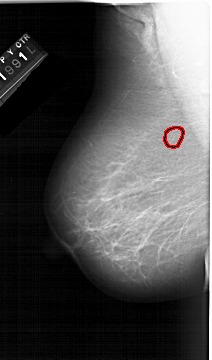

A_1324_1.RIGHT_CC

RIGHT_CC LINES 5626 PIXELS_PER_LINE 3046 BITS_PER_PIXEL 12 RESOLUTION 43.5 NON_OVERLAY

FILE: A_1324_1.LEFT_CC.OVERLAY

TOTAL_ABNORMALITIES 1

ABNORMALITY 1

LESION_TYPE CALCIFICATION TYPE PLEOMORPHIC DISTRIBUTION CLUSTERED

ASSESSMENT 4

SUBTLETY 3

PATHOLOGY BENIGN

TOTAL_OUTLINES 1

BOUNDARY